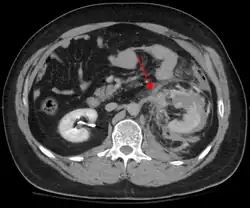

Contusão abdominal

O trauma abdominal contuso (TAB) representa 75% de todos os traumas contusos e é o exemplo mais comum dessa injúria.[4] 75% dos TAB ocorrem em colisões de veículos motorizados,[5] em que a desaceleração rápida pode impulsionar o motorista contra o volante, opainel de bordo ou o cinto de segurança,[6] causando contusões em casos menos graves ou ruptura de órgãos internos nos casos mais graves devido ao rápido aumento da pressão intraluminal, dependendo da força aplicada. Inicialmente, pode haver poucos indícios de que tenha ocorrido lesão abdominal interna grave, tornando a avaliação mais desafiadora e requerendo alto grau de suspeita clínica.[7]

Existem dois mecanismos físicos básicos a se levar em consideração no potencial de lesão de órgãos intra-abdominais: a compressão e a desaceleração.[8] A primeira ocorre a partir de um golpe direto, como um soco ou compressão contra um objeto resistente, como um cinto de segurança ou uma coluna de direção. Essa força pode deformar um órgão oco, aumentando sua pressão intraluminal ou interna e possivelmente levar à ruptura do mesmo.

A desaceleração, por outro lado, causa estiramento e cisalhamento nos pontos onde os conteúdos móveis do abdomen, como os intestinos, estão ancorados. Isso pode causar ruptura do mesentério intestinal e lesões nos vasos sanguíneos que passam por ele. São exemplos clássicos desses mecanismos ruptura no fígado por meio de seu ligamento redondo e lesões nas artérias renais.

Quando o trauma abdominal fechado é complicado por "lesão interna", o fígado e o baço (ver trauma esplênico fechado) são envolvidos com maior frequência, seguidos pelo intestino delgado.[9]